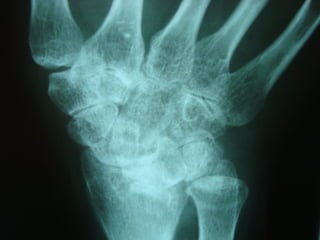

Achados radiográficosAchados radiográficos

 Osteopenia peri-articularOsteopenia peri-articular

 Diminuição do espaço articularDiminuição do espaço articular

 Presença de cisto e erosõesPresença de cisto e erosões

 Edema de partes molesEdema de partes moles

 Presença de deformidadesPresença de deformidades